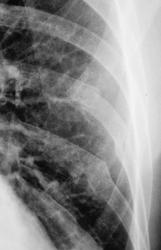

Пол пациента: Мужской пол Тип патологии: Травма Область исследования: Скелетно-мышечная система Методы исследования: Rg Травма. Пациент направлен на рентгенографию ребер слева https://radiomed.ru/sites/default/files/styles/case_slider_image/public/user/12/2.dscn1097.jpg?itok=gzM4pebU https://radiomed.ru/sites/default/files/styles/case_slider_image/public/user/12/3.dscn1097a.jpg?itok=BuHE6lDQ ID:26473 Пнд, 18/02/2013 - 20:55 #1 И.Бондаренко Не на сайте Был на сайте: 5 часов 32 минуты назад Зарегистрирован: 13.09.2011 - 22:55 Публикации: 9206 Свежий перелом 8 ребра по задне-подмышечной линии и ,наверное, старые переломы 8 и 9 ребер.

Свежий перелом 8 ребра по задне-подмышечной линии и ,наверное, старые переломы 8 и 9 ребер.